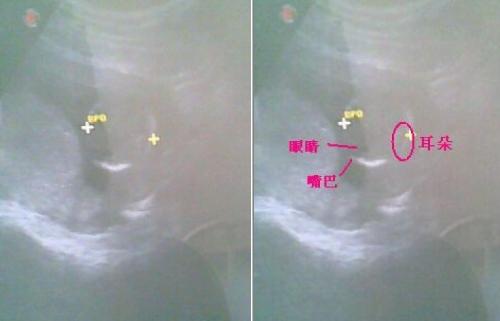

怀孕三个月胎儿图片